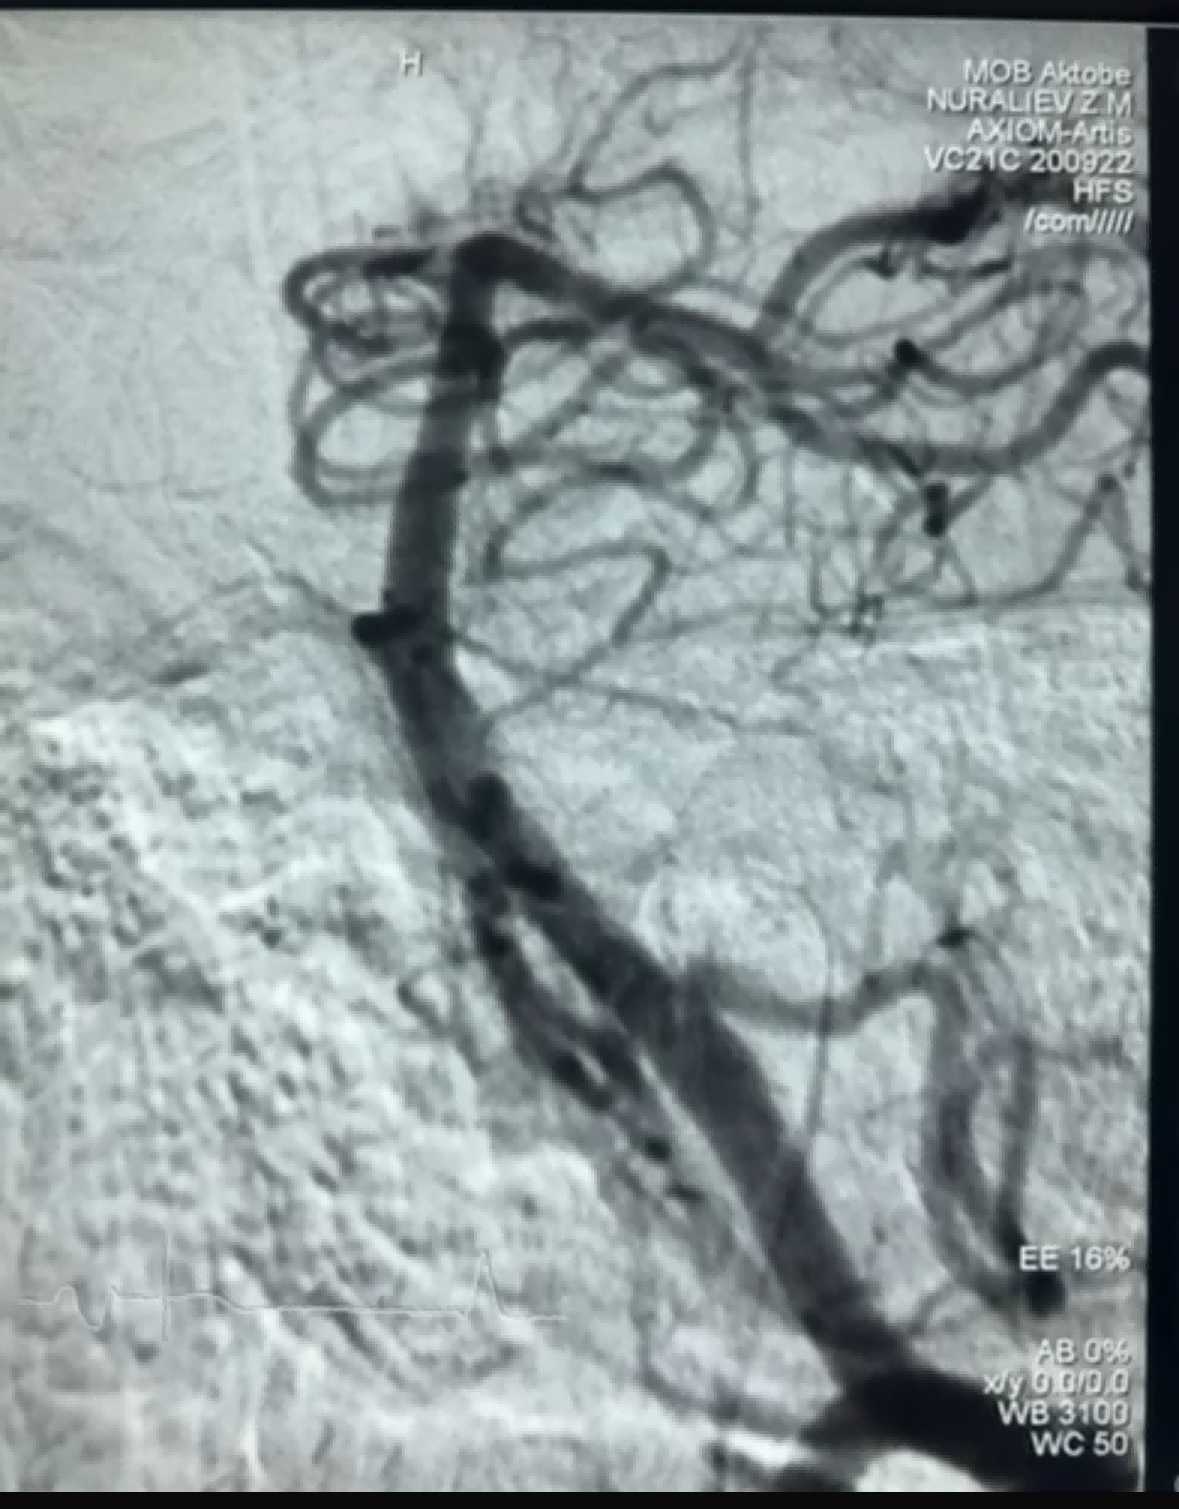

Nýlega var segabrottnám með góðum árangri með því að nota Dredger Stent Retriever frá NeuroSafe Medical Co., Ltd. Dredger Stent Retriever er með mjúkan þjórfé sem ekki er ífarandi, sem dregur verulega úr hættu á skaða á nánum, og hefur einstakt sérlaga gat hönnun sem fangar blóðtappa aðallega með því að klemma bilið breytingar.